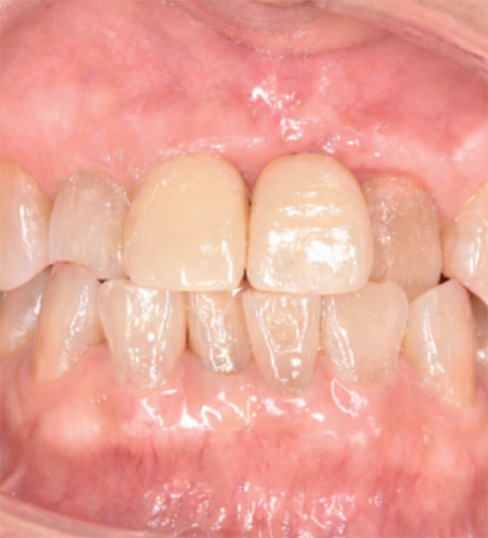

前歯部は見た目と機能の両立が重要な部位です。インプラント埋入時にGBR(骨造成)とCTG(結合組織移植)を併用し、審美性と安定性の両立を図りました。

口腔内写真

(術後)

治療後